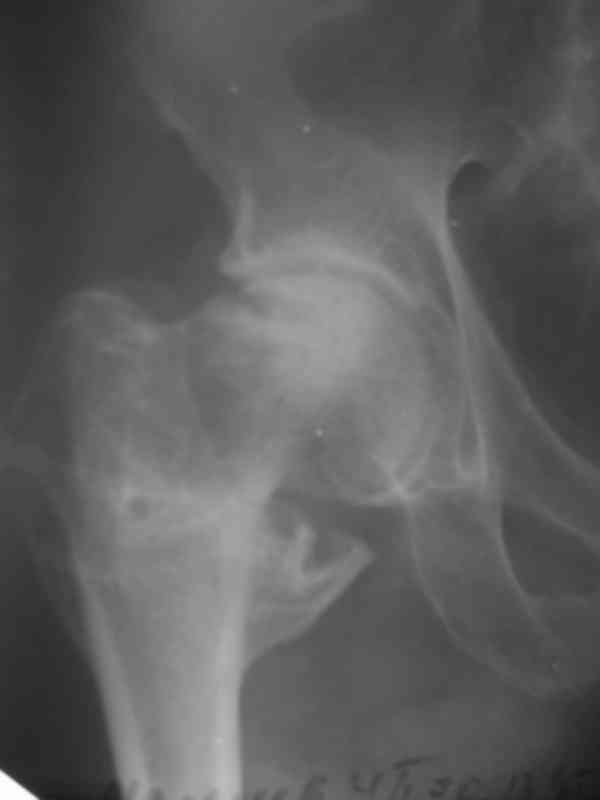

Первый перелом в июне 2002 года - перелом шейки бедра. Лечение консервативно, на данный момент имеем такую картину(см. R-gr.) Падение на бедро в июне 2006 года - не диагностирован второй косой перелом бедра на этой же стороне (просто сказали - полежать) И вот больной с переломом в/3 костей голени (опять же на этой стороне) попадает к нам в отделение. На момент поступления в н/3 бедра истинный ложный сустав. Решили первым этапом зафиксировать бедро с голенью АВФ с дистракцией на бедре (восстановить длину бедра), одновременно для жесткости пришлось зафиксировать колено. Ч/з месяц колено распустили, начали его разработку.На данный момент думаем довести голень на аппарате (или может -ЭКСПЕРТ???), а бедро после устранения всех видов смещения заштифтовать стержнем с блокированием для низких или мыщелковых переломов. НО смущает выраженный остеопороз - удержат ли запирающие винты отломки бедра!С Уважением Владимир Бахарев.

АВФ. Кстати, на этих снимках наличие ложного сустава бедра вызывает большие сомнения. Скорее можно говорить о несросшемся кососпиральном переломе бедренной кости и переломе в\3 б\берцовой кости.